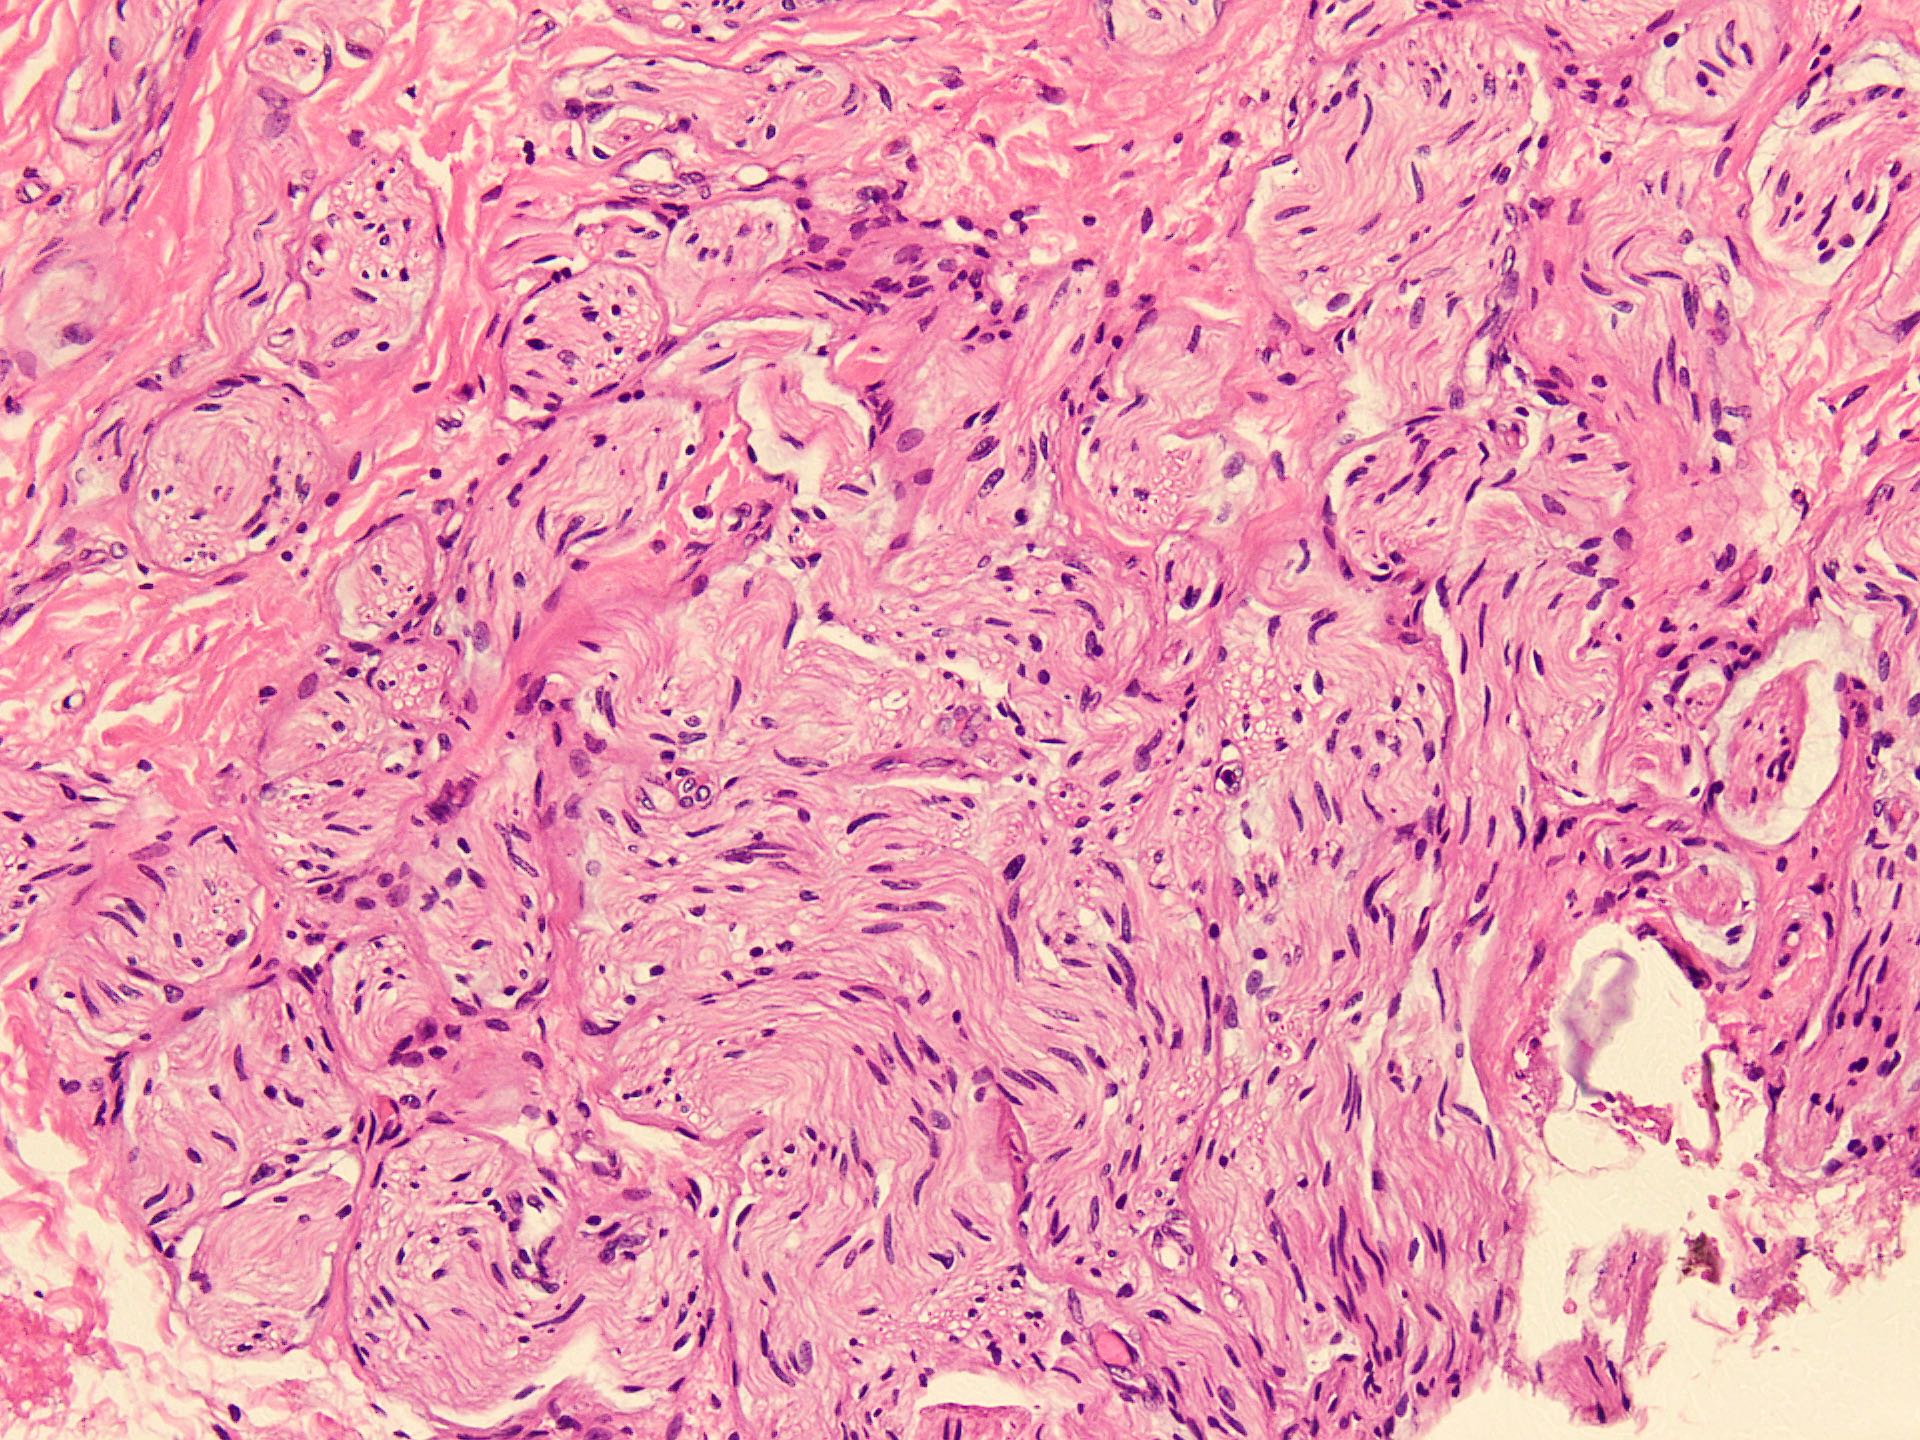

Microscopic (histologic) description

- Circumscribed, unencapsulated spindle cell proliferation arranged in short bundles comprised of axons, Schwann cells, endoneurial cells and perineurial cells (World J Clin Cases 2020;8:3821, Acta Biomed 2020;91:122, StatPearls: Neuroma [Accessed 21 September 2022])

- Peripheral palisading is not present (World J Clin Cases 2020;8:3821)

- Prominent scar tissue with dense collagen may be present (Acta Biomed 2020;91:122, StatPearls: Neuroma [Accessed 21 September 2022])

- Dystrophic calcifications are rarely present (Acta Biomed 2020;91:122)

Microscopic (histologic) images

- Microscopy: The sections examined show a circumscribed, unencapsulated lesion composed of variable sized, closely packed nerve bundle along with scar tissue in the background.